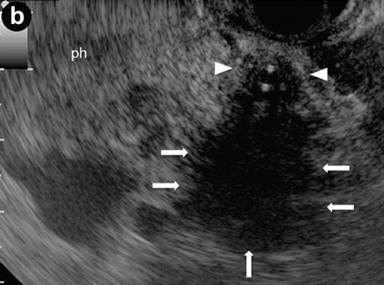

Patient#6: Diffuse form of autoimmune pancreatitis.

A 25-year-old man presented with jaundice, dilated bile ducts and an enlarged pancreatic gland at sonography; IgG4 levels were elevated (802 mg/dL). Endoscopic retrograde cholangiography (ERC) (Image 6a) showed stenosis of the distal common bile duct (arrows), and a stent was positioned. EUS linear scans (Image 6b) confirmed a substantially and diffusely enlarged pancreas, (arrows: pancreatic head), with echopoor echotexture and hyperechoic septa; the common bile duct, containing the stent, showed a three-layered, "sandwich-pattern" and thickening of the wall (arrowheads).

|

Image 6 |